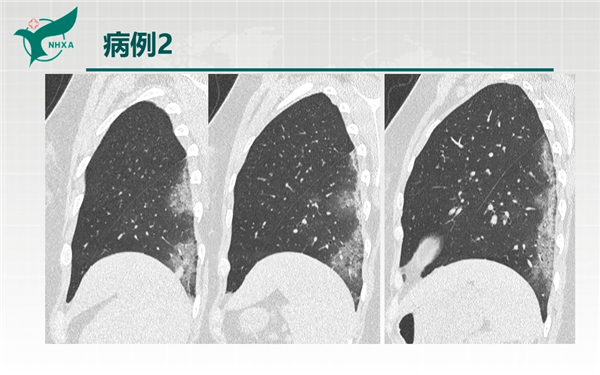

【病例分享】新型冠狀病毒肺炎3例(西安市第九醫(yī)院)

幻燈片6.jpg